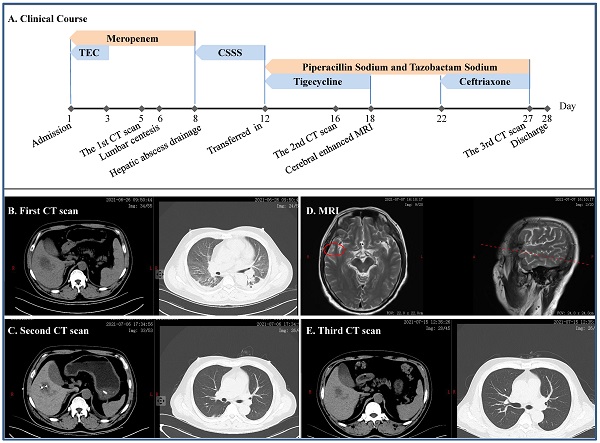

Challenge of evolving Klebsiella pneumoniae infection in patients on hemodialysis: from the classic strain to the carbapenem-resistant hypervirulent one

Shuai Zhou, GuangWei Ren, YuKun Liu, XiaoMing Liu, LiHong Zhang, ShuFeng Xu, Tao Wang

Int. J. Med. Sci. 2022; 19(3): 416-424. doi:10.7150/ijms.69577